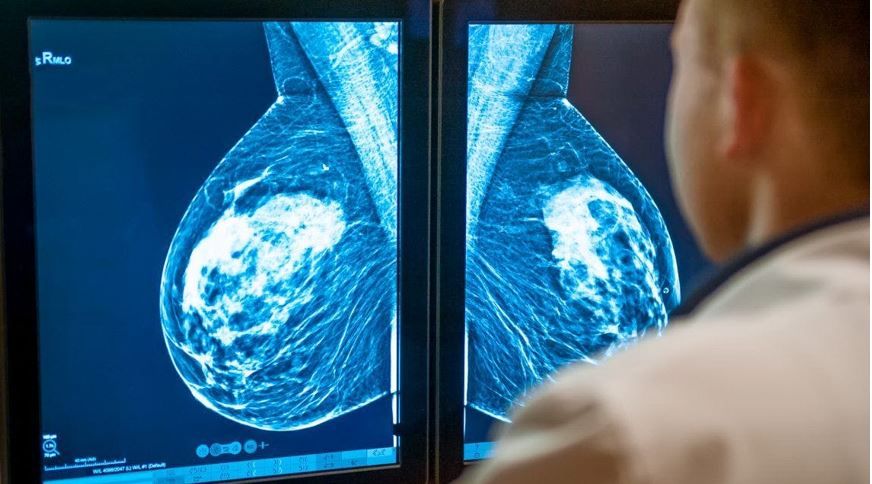

The United States Preventive Services Task Force (USPSTF) announced on April 30 a final recommendation statement on screening for breast cancer, lowering the age for initiation of screening mammography for women at average risk from age 50 to age 40 years and recommending ongoing surveillance every other year through age 74 years.1

Changes in prevalence of breast cancer have played a role in the evolution of the Task Force recommendations. The rates of breast cancer for women in their 40s increased gradually between 2000 and 2015 but have risen more noticeably since then, increasing by approximately 2% per year, according to the USTSPF.2 “By starting to screen all women at age 40, we can save nearly 20 percent more lives from breast cancer overall," Task Force chair Wanda Nicholson, MD, MPH, MBA, said in the USPSTF announcement.2 "This new approach has even greater potential benefit for Black women, who are much more likely to die of breast cancer.”2